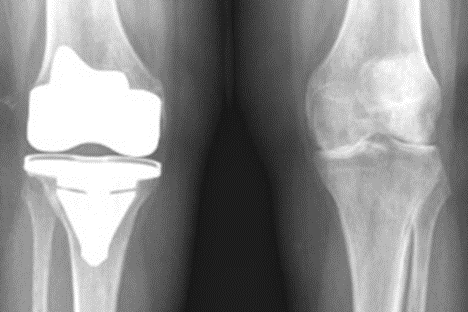

Etter at du har fått kneprotese kan du håpe på å kunne gå turer i terrenget, spille golf og gå turer på ski. Det er ikke anbefalt å drive idrett som medfører hopping og vridning som fotball. Når smerten ved gange eller i ro er moderat til sterk til tross for annen behandling foreslått over, og røntgenbilder viser slitasje av brusken (redusert tykkelse) i kneet (figur 1: Artrose med redusert brusk i kneet), kan det være aktuelt å tilby deg kneproteseoperasjon. Din fastlege kan da henvise deg til din lokale ortopediske sykehusavdeling, du blir der undersøkt av en ortopedisk kirurg.

Figur 1: På bildet til høyre sees slitasje av brusken i kneet. Det er ingen mellomrom mellom lårbenet og leggbenet. På bildet til venstre sees en protese. Det hvite representerer metall og mellomrommet plast (polyetyen).

I Norge brukes vanligvis sementerte kneproteser uten kneskjellskomponent (uten patellakomponent figur 1 og 2:) (Figur 3 kneprotese med patellakomponent).

Figur 2: Kneprotese sett fra siden. Det hvite metallet erstatter den mengde ben og brusk som er saget bort, mellomrommet mellom de to hvite delene som er noe mørkere representerer plasten (polyetylen) som lårbensdelen beveger seg på. Det litt lysere hvite mellom protese og ben er sement som fester protesen til benet.